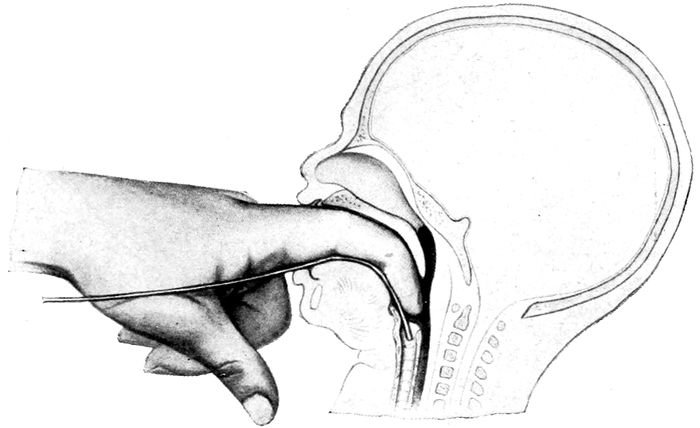

| 117. |

Method of passing the tracheal catheter |

279 |